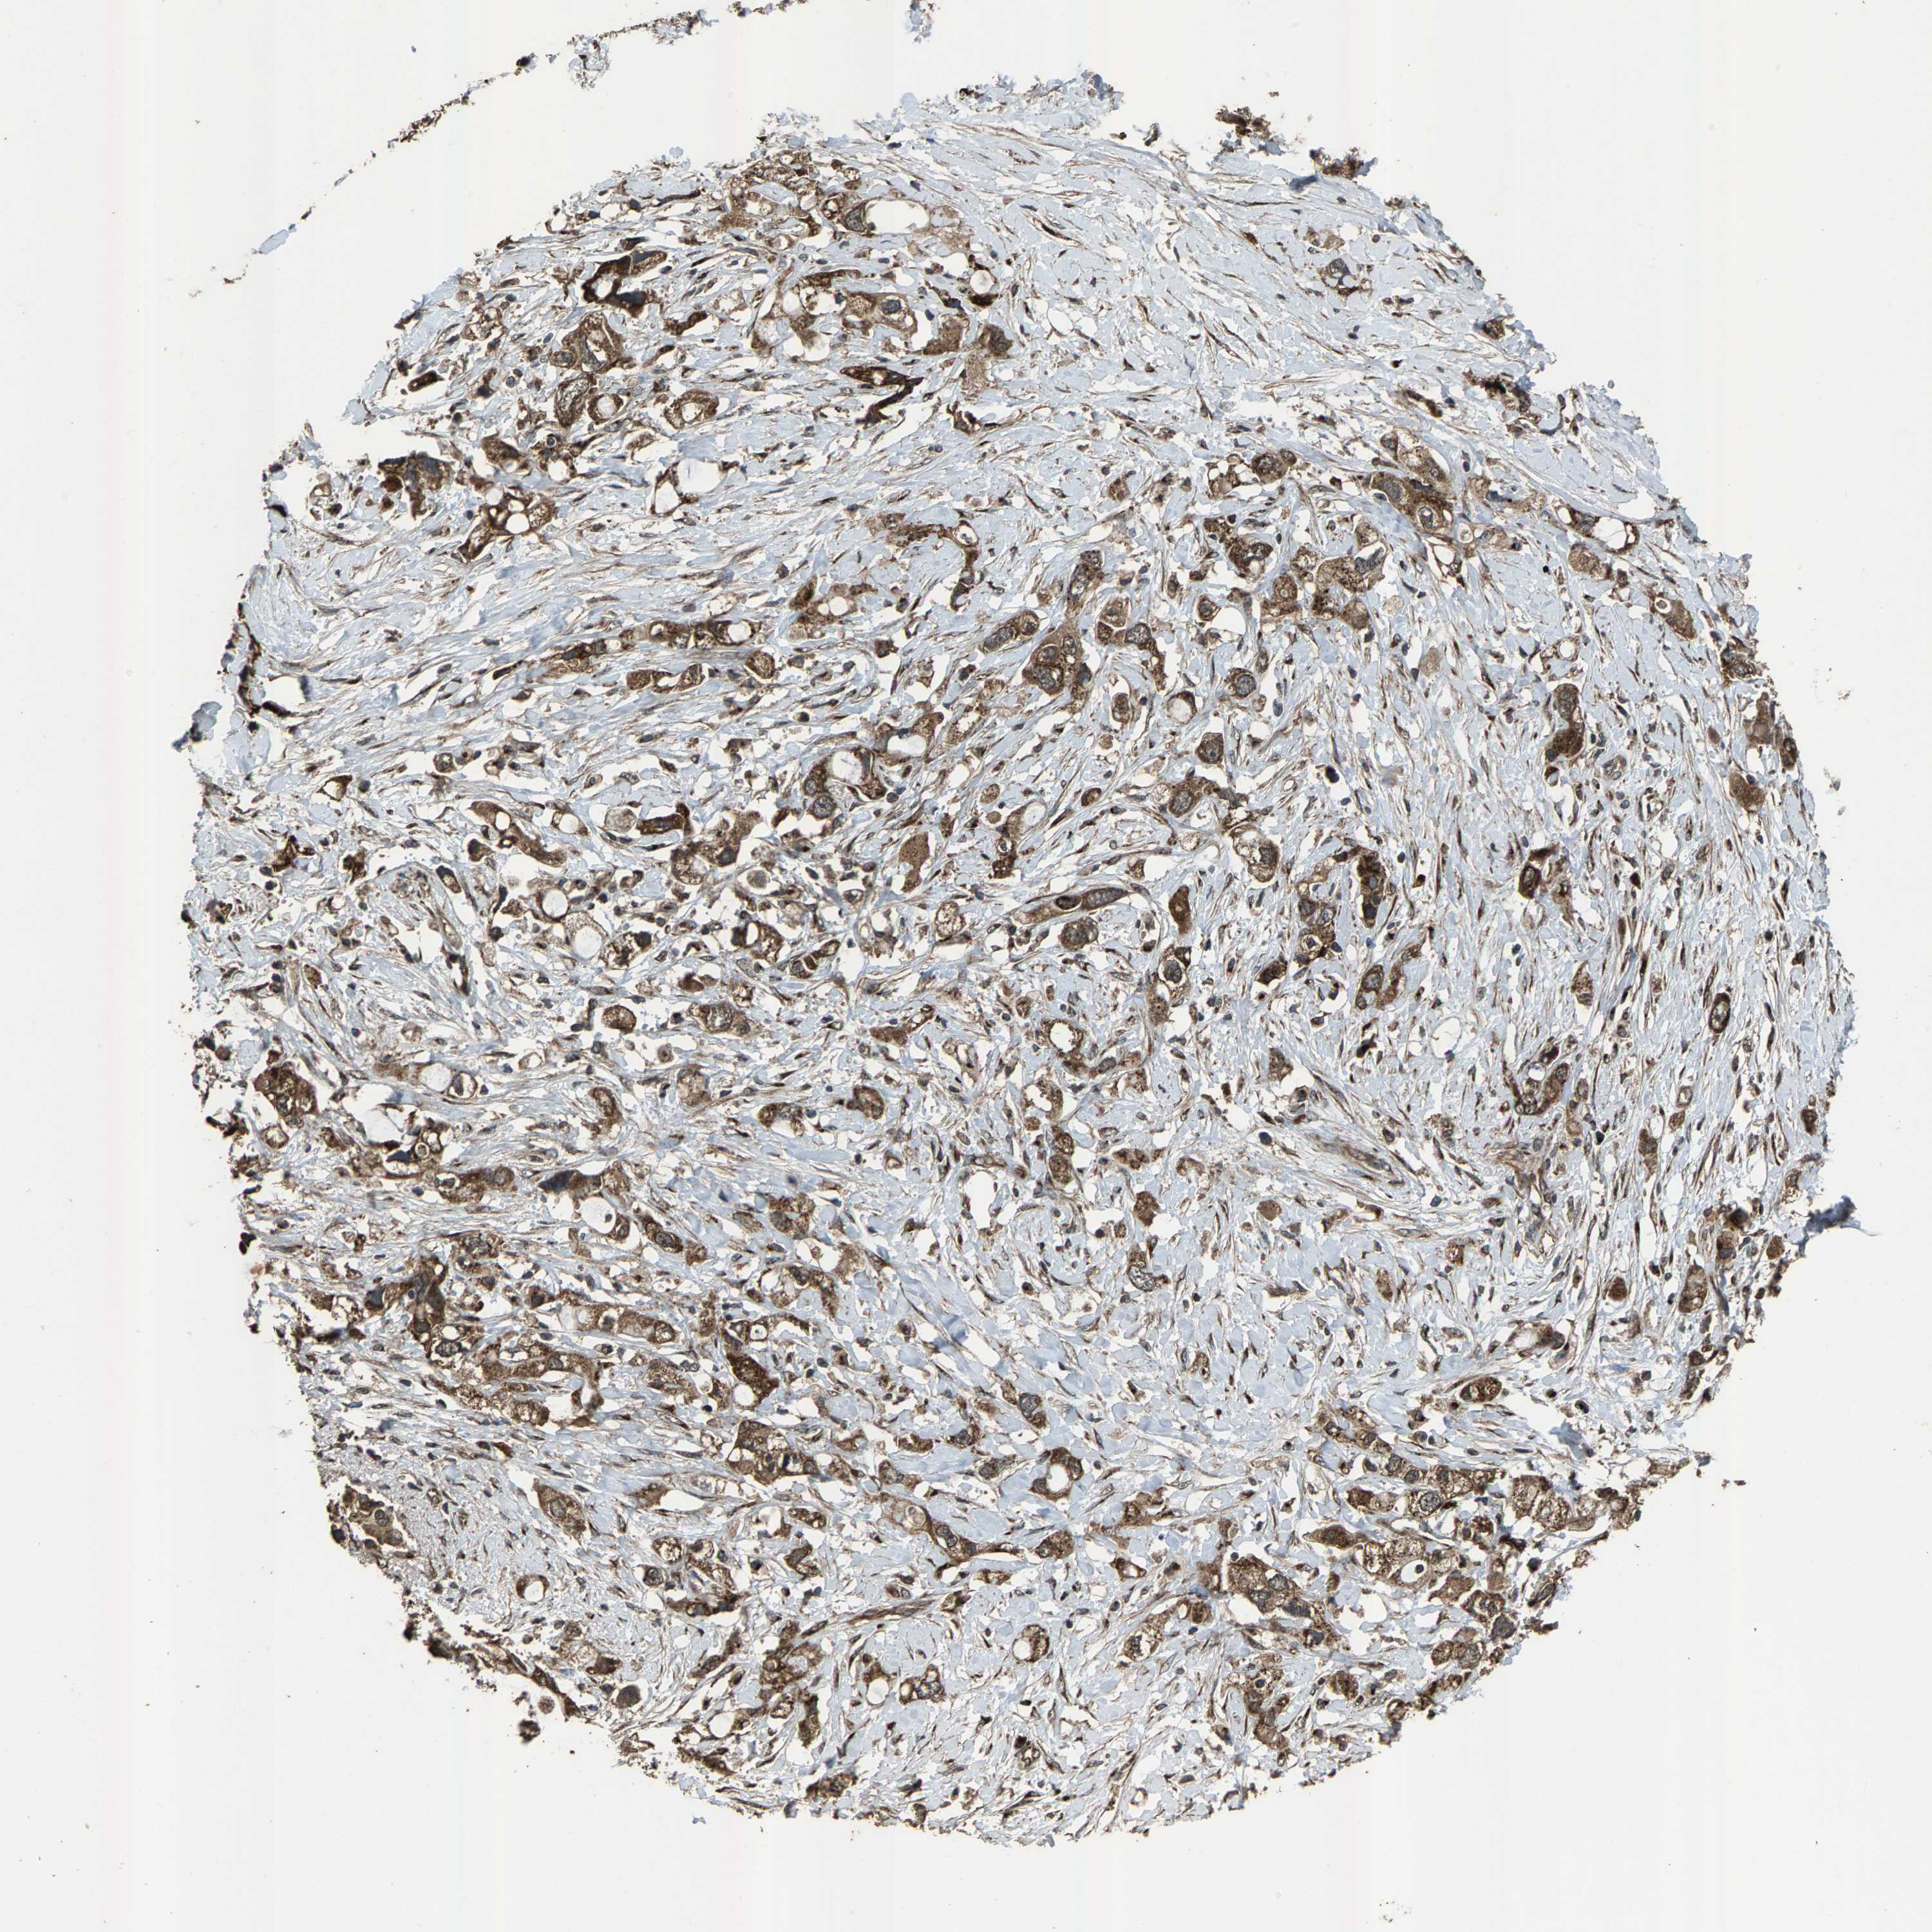

PANCREATIC CANCER - Protein expressioni

A mouse-over function shows sample information and annotation data. Click on an image to view it in a full screen mode. Samples can be filtered based on level of antibody staining by selecting one or several of the following categories: high, medium, low and not detected. The assay and annotation is described here.

Note that samples used for immunohistochemistry by the Human Protein Atlas do not correspond to samples in the TCGA dataset.

Antibody stainingi

Antibody staining in the annotated cell types in the current human tissue is reported as not detected, low, medium, or high, based on conventional immunohistochemistry profiling in selected tissues. This score is based on the combination of the staining intensity and fraction of stained cells.

Each image is clickable and will lead to virtual microscopy that enables deeper exploration of all samples and also displays staining intensity scores, fraction scores and subcellular localization as well as patient and tissue information for each sample.

Antibody HPA021374

Antibody HPA023161

Antibody HPA024631

Staining

High

Medium

Low

Not detected

Intensity

Strong

Moderate

Weak

Negative

Quantity

>75%

75%-25%

<25%

None

Location

Nuclear

Cytoplasmic/membranous

Cytoplasmic/membranous,nuclear

Adenocarcinoma, NOS